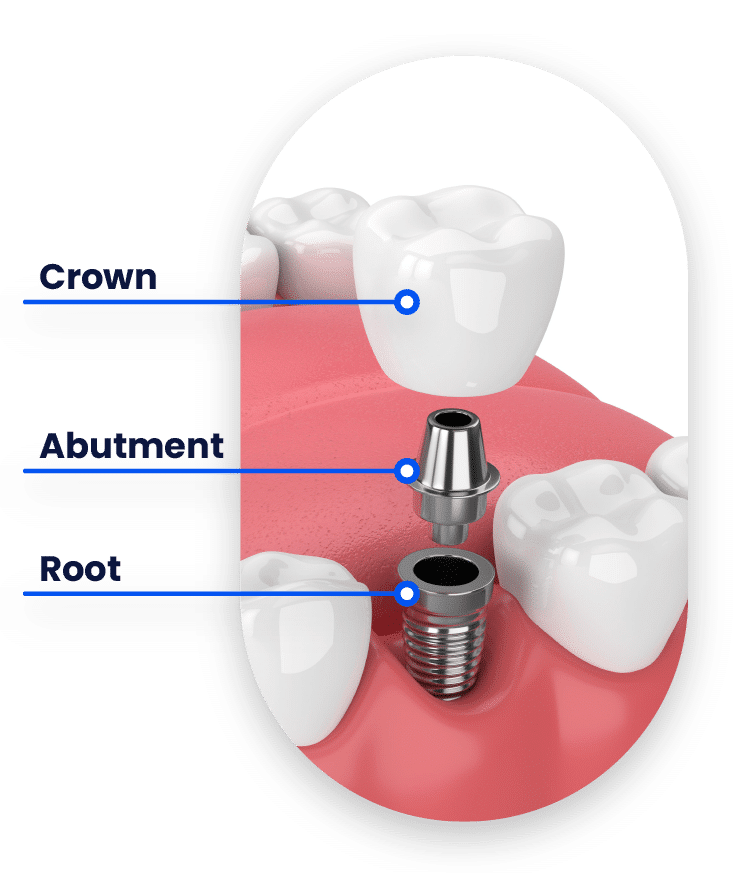

What are Dental Implants?

A dental implant is essentially a sophisticated, three-part artificial tooth. It consists of a root, which is a titanium screw embedded into the jawbone, an abutment that acts as a connector placed on top of the implant, and a crown, the visible part that mirrors the appearance of a natural tooth. The materials utilized in the construction of dental implants, including titanium and ceramic, are biocompatible and carefully chosen to mimic the function and aesthetic of natural teeth, thus ensuring a seamless blend with the patient’s existing dental structure.

The dental implant process is meticulously planned and executed to ensure optimal results. It starts with a comprehensive evaluation where the patient’s oral health is thoroughly assessed, followed by the creation of a detailed treatment plan. The surgical phase involves the doctor placing the implant into the jawbone. After this, the patient enters a healing phase during which osseointegration, the process of the implant bonding with the bone, occurs. This integration is critical to providing a solid foundation for the artificial tooth. Lastly, the abutment and crown are fitted, completing the restoration and giving the patient a fully functional and aesthetically pleasing dental solution.